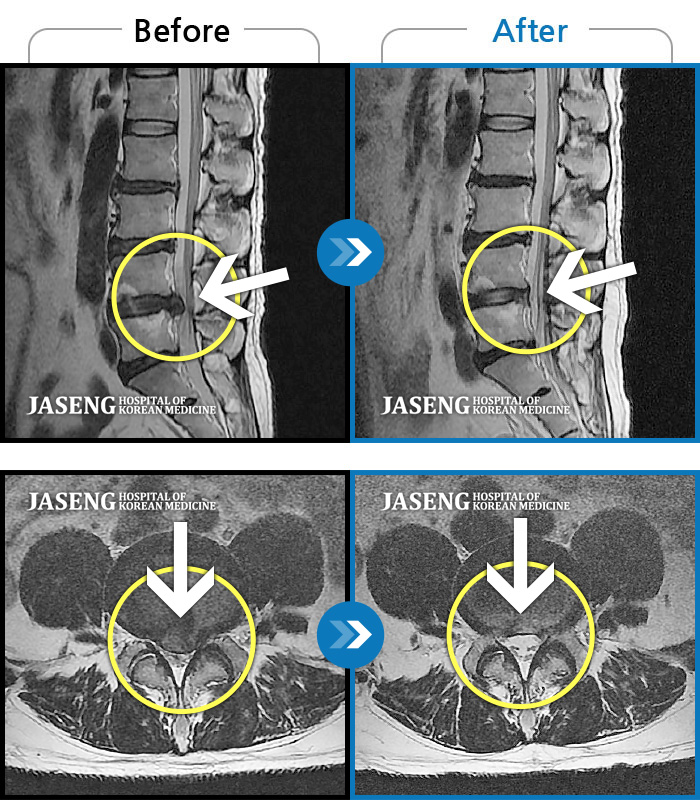

ȯںп Ǹ ǿ ԿǾ, ο ġ ۿ Ƿ ġḦ Ͻñ ٶϴ.